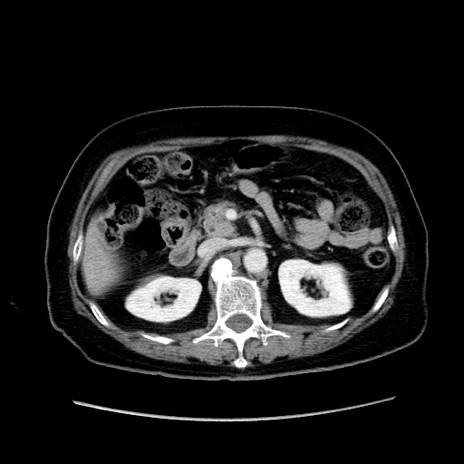

症例19(横断像)

【症例】80歳代女性

【主訴】下腹部痛

【現病歴】約8時間前より下腹部痛の出現あり、救急外来受診。

【既往歴】両側付属器切除

【身体所見】意識清明、下腹部正中に手術痕あり、その部位に一致して圧痛と反跳痛あり。腸蠕動音は亢進。

【データ】WBC 9300、CRP 0.15